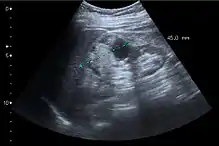

Renal ultrasonography

On renal ultrasonography, a solid renal mass appears in the US exam with internal echoes, without the well-defined, smooth walls seen in cysts, often with Doppler signal, and is frequently malignant or has a high malignant potential. The most common malignant renal parenchymal tumor is renal cell carcinoma (RCC), which accounts for 86% of the malignancies in the kidney. RCCs are typically isoechoic and peripherally located in the parenchyma, but can be both hypo- and hyper-echoic and are found centrally in medulla or sinus. The lesions can be multifocal and have cystic elements due to necrosis, calcifications and be multifocal (Figure 8 and Figure 9). RCC is associated with von Hippel–Lindau disease, and with tuberous sclerosis, and US has been recommended as a tool for assessment and follow-up of renal masses in these patients.[3]